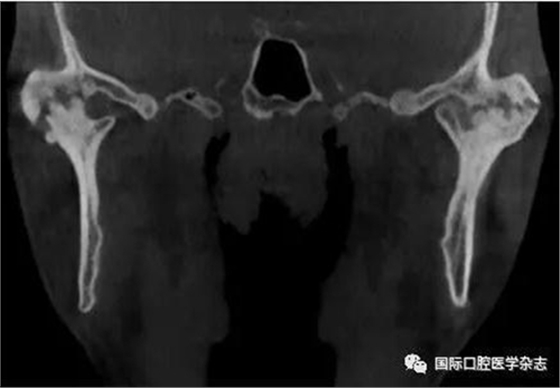

(3)骨關節(jié)?。▓D2):屬于顳下頜關節(jié)器質性改變,主要發(fā)生在髁突的骨質變化,其次是關節(jié)窩及關節(jié)結節(jié)的改變。影像學檢查發(fā)現骨、軟骨和關節(jié)盤有退行性改變,關節(jié)運動時可聞及連續(xù)摩擦音。伴有滑膜炎或關節(jié)囊炎時,有開口痛和咀嚼痛,開口受限,這時可稱骨關節(jié)炎。

圖 2 骨關節(jié)病